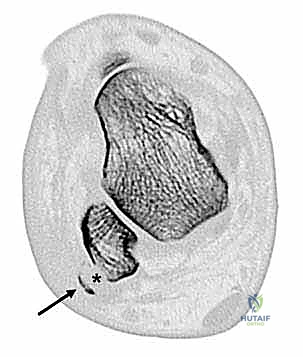

* تسطح الميزاب الشظوي (Shallow Fibular Groove): بدلاً من أن يكون الميزاب مقعراً وعميقاً لاحتضان الأوتار، يكون مسطحاً أو حتى محدباً (Congenitally convex)، مما يجعل انزلاق الأوتار مسألة وقت.

في الماضي، كانت الجراحات التقليدية تعتمد على حفر الميزاب العظمي بشكل مباشر من الخارج، مما يؤدي إلى تدمير الغضروف الليفي الزجاجي (Fibrocartilage) الذي يبطن الميزاب، والذي وظيفته تسهيل انزلاق الأوتار بسلاسة. تدمير هذا الغضروف كان يؤدي إلى احتكاك الأوتار بالعظم الخشن، مما يسبب التهابات مزمنة وتمزقات لاحقة.

أما في التقنية غير المباشرة، يقوم الدكتور هطيف بإجراء هندسي عبقري: يتم عمل نافذة عظمية صغيرة أو استخدام مثقاب دقيق (Drill) لإزالة العظم الإسفنجي (Cancellous bone) من داخل عظمة الشظية (من تحت الغضروف)، ثم يتم الضغط (Tamping) على القشرة العظمية المبطنة بالغضروف لتهبط إلى الداخل.

النتيجة؟ ميزاب عميق جداً يحتضن الأوتار بقوة، مع الحفاظ الكامل على الغضروف الأملس السليم بنسبة 100%.